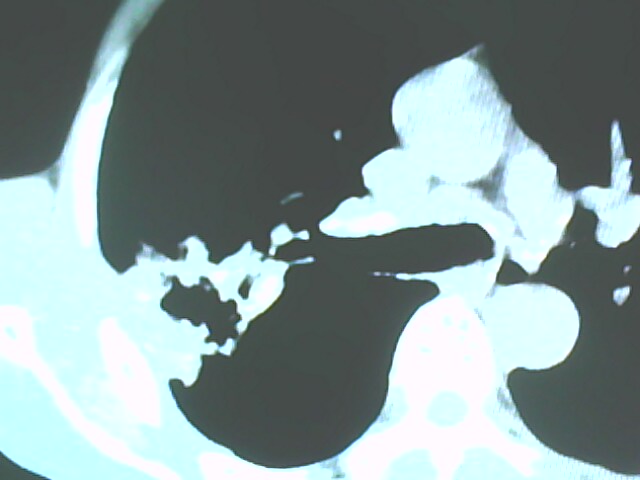

患者,男,66岁,以咳嗽、咳痰伴胸痛来就诊。

胸片提示右上肺占位病变。请各位老师看看ct。

请各位老师看看,考虑:癌性空洞吗?

考虑癌性空洞可能性大,空洞内壁不规则,病灶周围模糊,分叶、有毛刺

考虑右肺上叶后段周围型肺癌并癌性空洞形成。

典型癌性空洞(偏心性,壁厚薄不均,内壁不光整),周围毛刺较僵硬,且有刺突征和血管聚集征